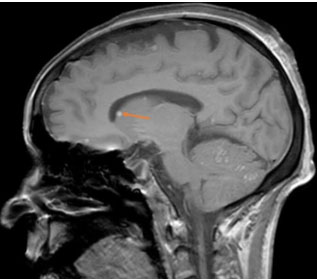

Brain MRI showed multiple nodular lesions in the frontal, parietal, occipital, and temporal lobes, in addition to the cerebellar hemispheres, not exceeding 2 cm in size, hyperintense on T1, hypointense on T2 and T2*, with nodular and ring-like enhancement after contrast (Figure 3, Figure 4, Figure 5), suggesting a melanomatous origin, in favor of a cerebral relapse of the anorectal melanoma.

Figure 3: A sagittal T1 pre-contrast MRI image showing a hyperintense nodular lesion in the right caudate nucleus (arrow).